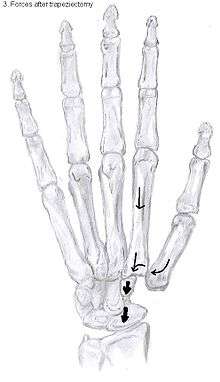

The large forces, which the CMC1 joint has to withstand, are considered to be another cause of CMC OA.[10] During daily manual activities, such as grabbing and pinching, the thumb is constantly being used. The forces generated by these movements have an enlarged impact on the CMC1 joint because of the leverage within the thumb. This makes the joint even more sensitive to wear and tear.[10]

This high mobility is due to the little intrinsic osseous stability of the joint. This causes the CMC1 joint to be more unstable compared to the CMC joints of the other fingers.[9] Because of this instability, the joint is more susceptible to be damaged.[10] To remain stable the CMC1 joint has to rely on the surrounding ligaments for support. These ligaments provide the ability to subject high pressure loads, particularly during pinch and grasp manoeuvres.[11]